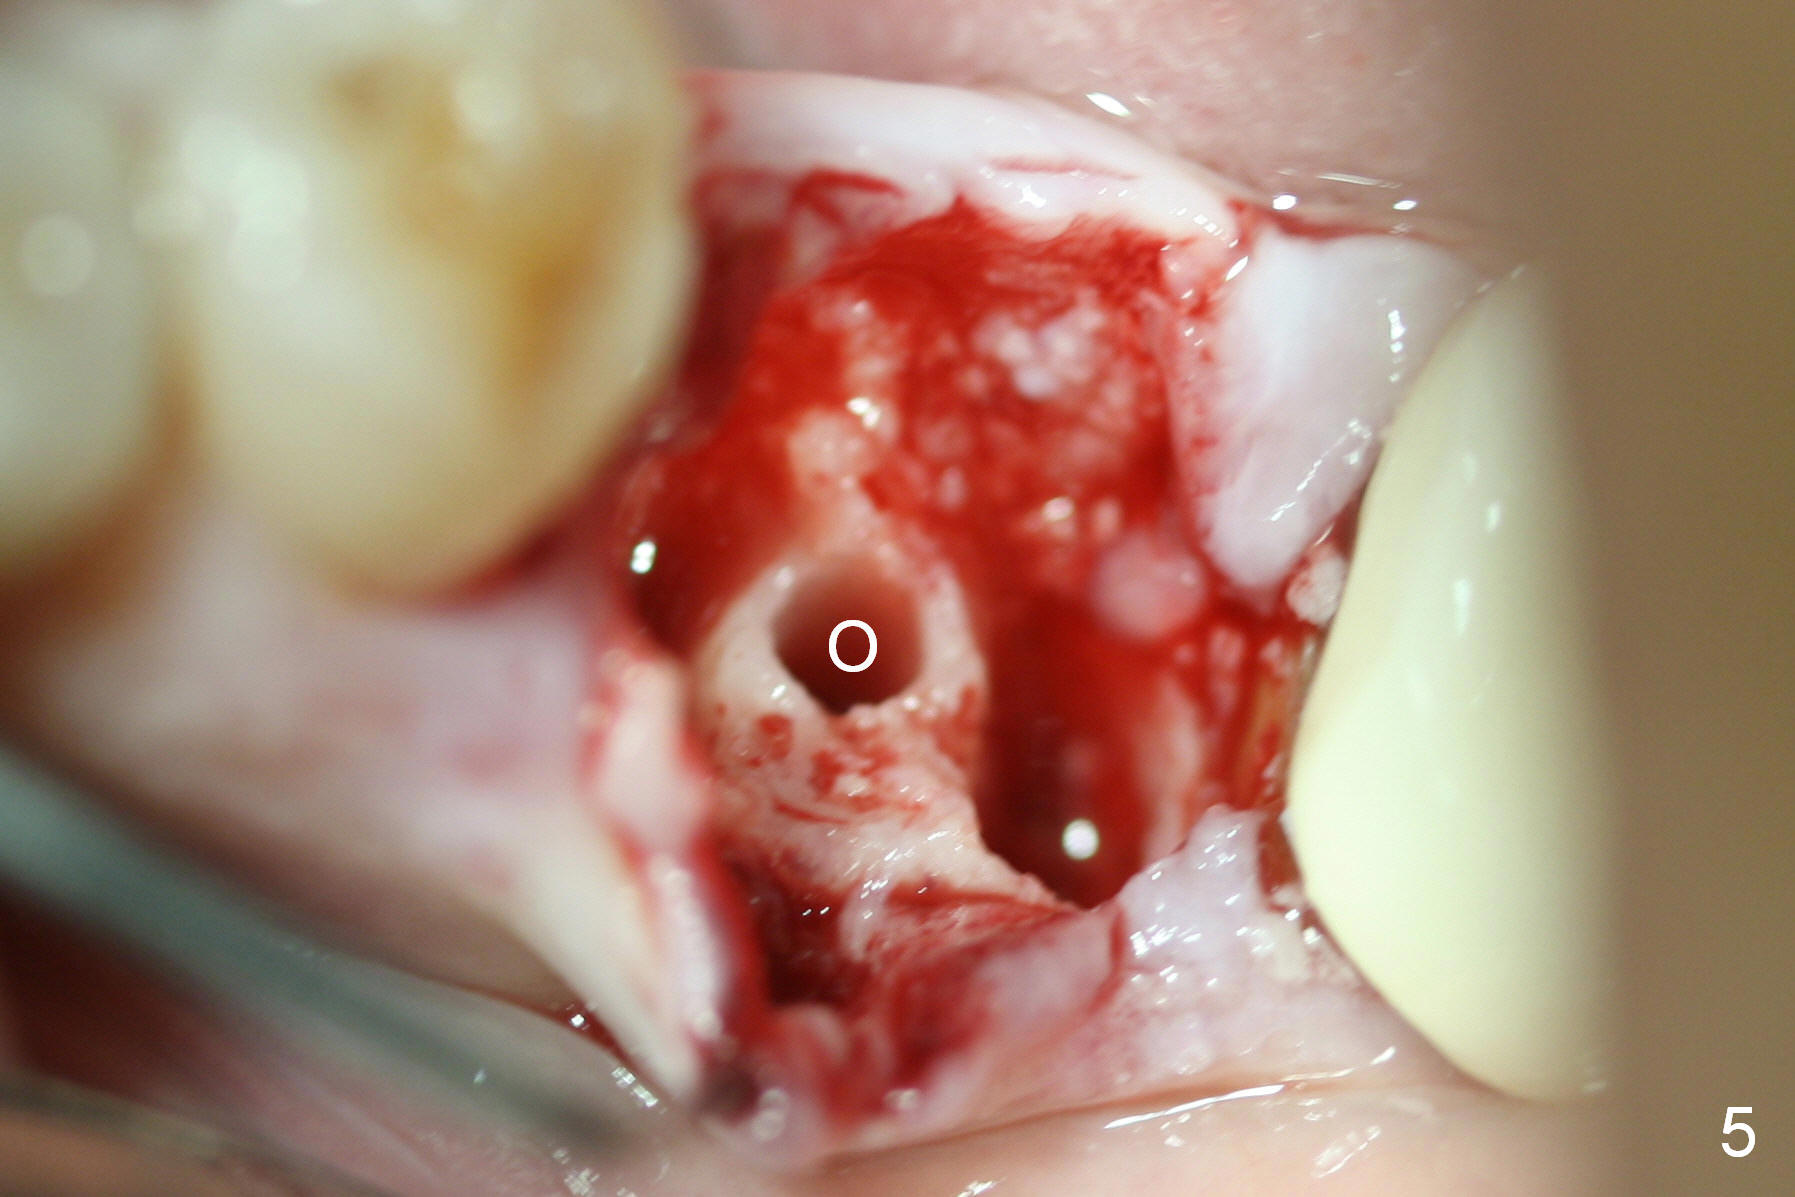

A 47-year-old lady lives out of town and presents to clinic with chief complaint "lower left back tooth easily bleeding with food impaction". Dental history and examination reveals failure of endo retreat of the tooth #19 (Fig.1), buccal gingival swelling (S), open access (A) and furcal and mesial periapical radiolucency (Fig.2 *). She is pleased to know availability of immediate implant and immediate provisional and accepts and receives the treatment at the same visit. The immediate implant (tissue-level) is designed to be as large as 7 mm and as long as 17 mm (Fig.3). To reduce paresthesia (yellow dashed line: the possible upper border of the Inferior Alveolar Canal)), a shorter implant (14 mm long in red line) is preferred. The tooth is extracted with sectioning. Granulation tissue is removed from the furca. The buccal plate appears to be intact. The septum is flat (Fig.4,10a S). Osteotomy starts in the middle of the septum with a 1.2 mm drill (Fig.10b red circle). As osteotomy increases in diameter (Fig.5 O), the apical end appears to be deviated mesiobuccally (Fig.10c large red circle). When a 6x17 mm tapered tap is being placed 14 mm deep (Fig.6 T), vibration of the buccal plate is seemingly felt at the apex (Fig.10d green circle). Further osteotomy may perforate the buccal plate. A 6x14 mm tissue-level implant is placed with >60 Ncm of insertion torque (Fig.7,8 I), followed by a 5x3 mm abutment (A) and bone graft (* in the remaining socket gap). An immediate provisional is cemented without occlusal contact (Fig.9 P).